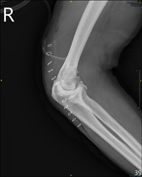

圖三、Outerbridge-Kashiwagi手術術後X光片